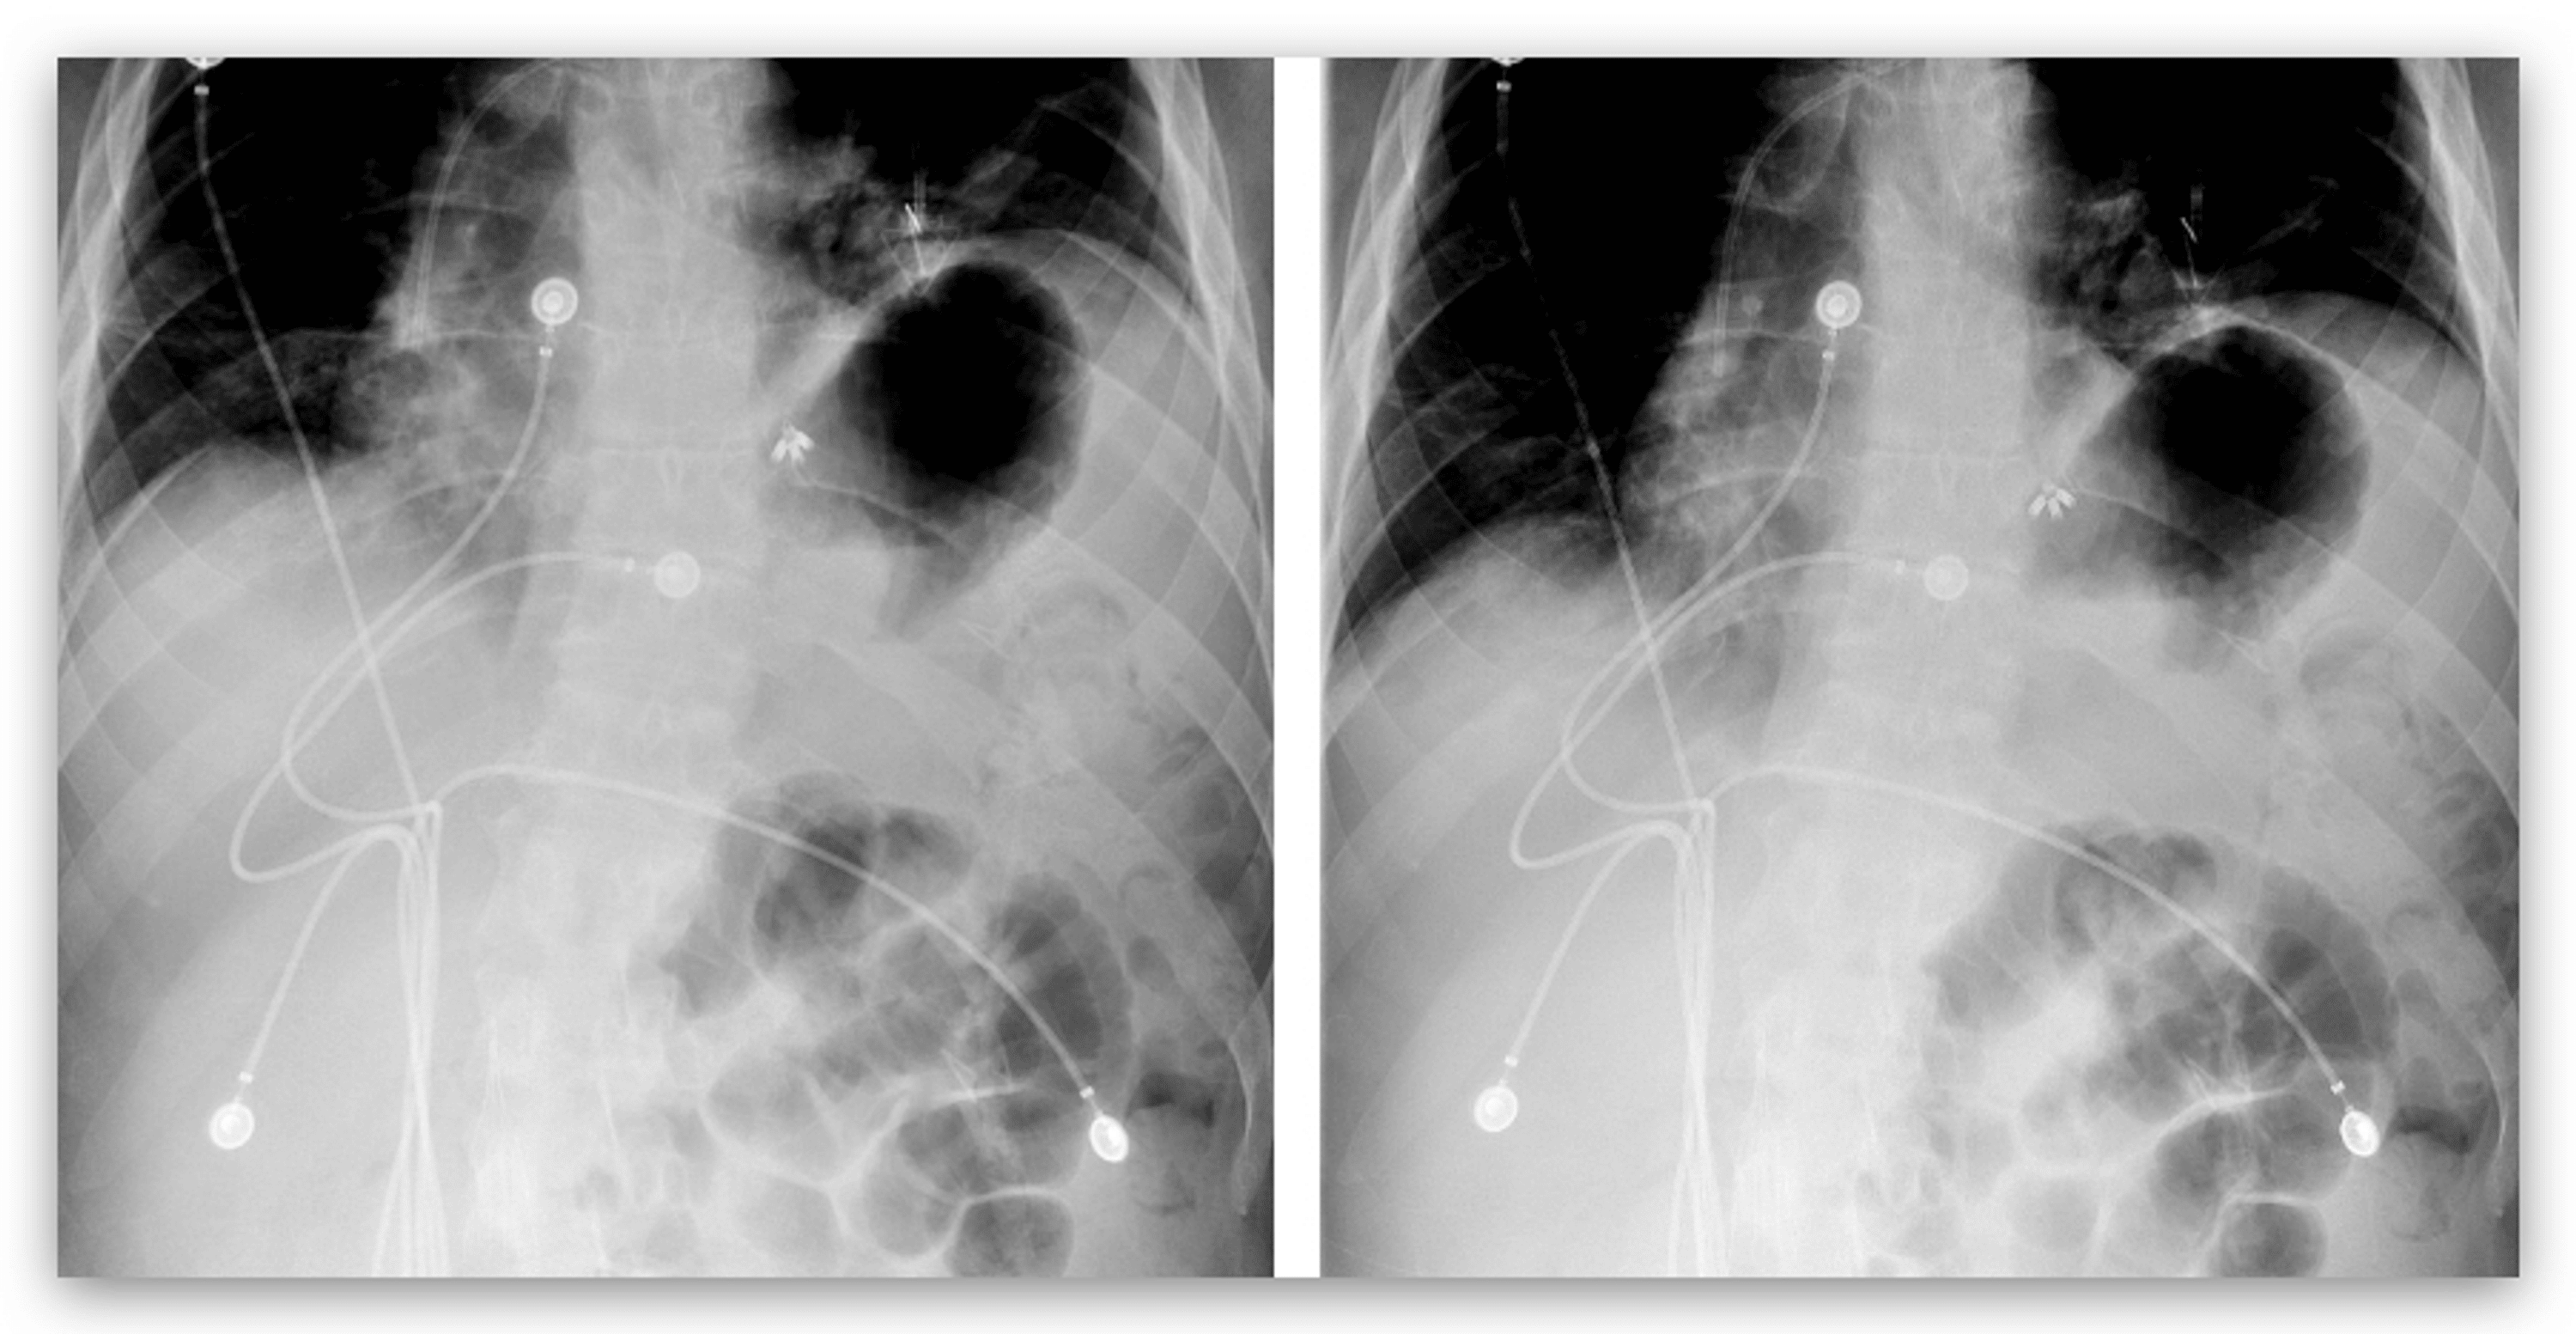

Imaging of the Diaphragm Anatomy and Function RadioGraphics Diaphragmatic Excursion Decreased The study establishes that copd affects diaphragmatic excursion and lung function. Decreased diaphragmatic excursion may be detected by percussion of the lower rib cage at end expiration. Diaphragmatic excursion values presented in this study can be used as reference values to detect diaphragmatic dysfunction in. In patients with chronic obstructive pulmonary disease (copd), the maximum level of diaphragm excursion (de. Diaphragmatic Excursion Decreased.